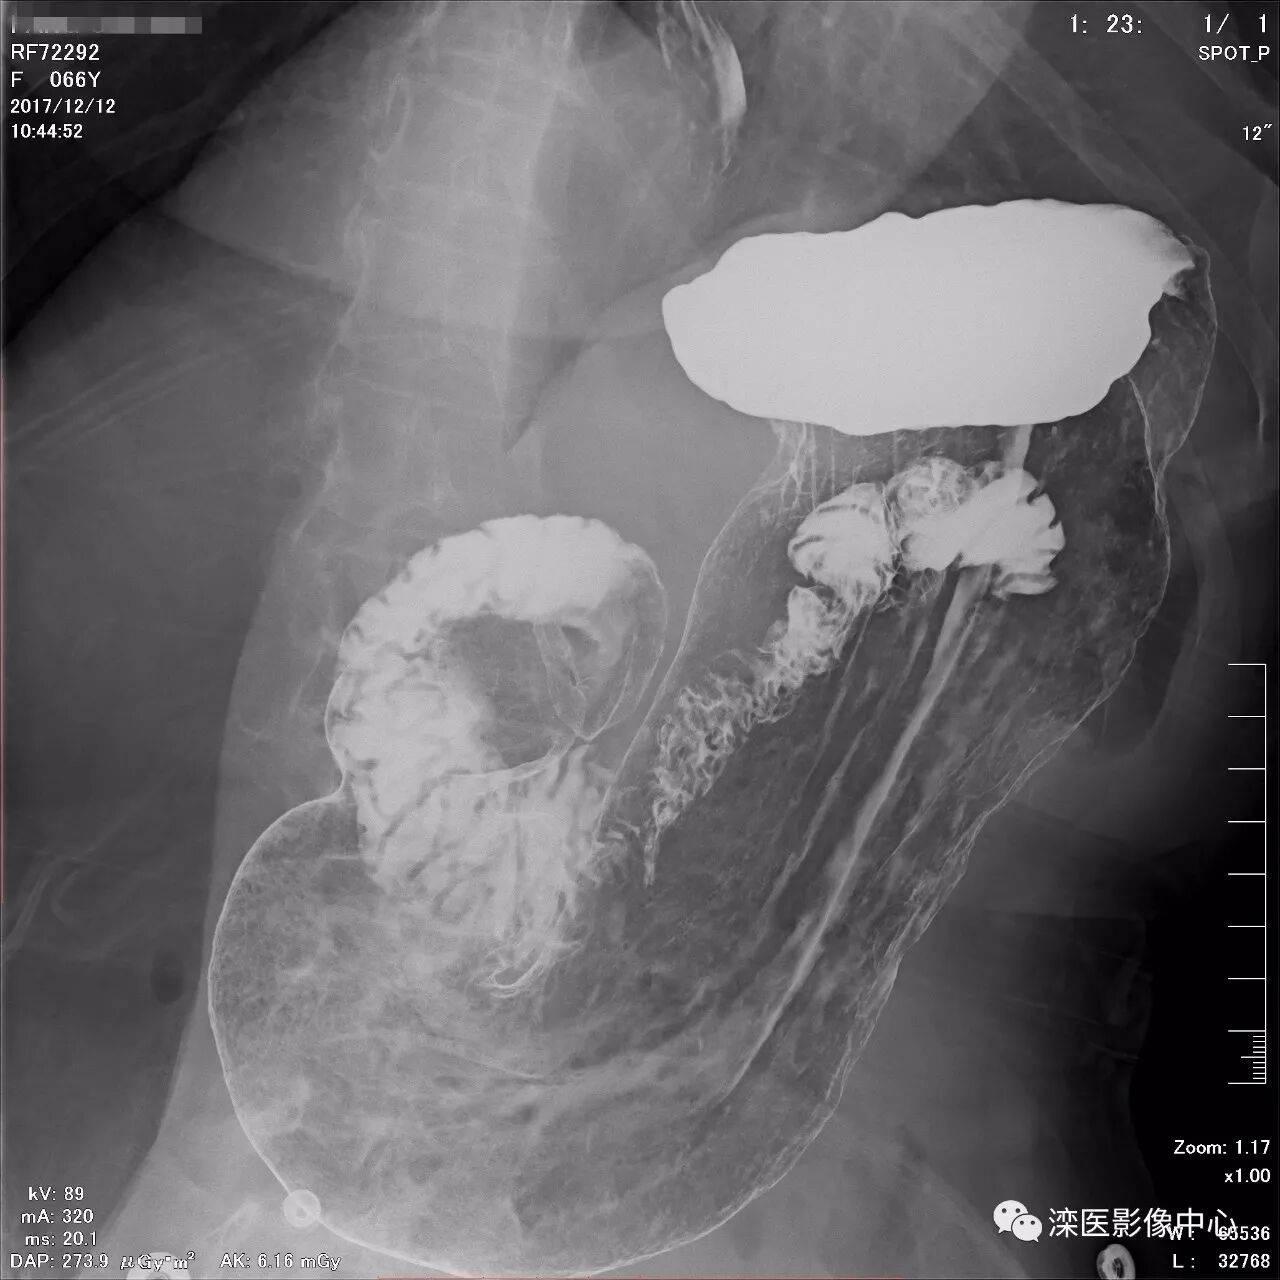

正位,显示食管、贲门及喉咽部的粘膜像)

(左前斜位,显示食管、贲门的粘膜像

(右前斜位,显示食管、贲门的粘膜像)

(以上图像是患者立位+卧位,通过变换体位,多角度显示了贲门胃底、胃体、胃大弯、胃小弯、胃窦、幽门及十二指肠球部、降部、水平部、升部的粘膜像和充盈像。本例患者女性,66岁,此次检查可以清晰显示胃小区结构,检查中发现患有慢性胃炎、胃下垂、十二指肠降部憩室)